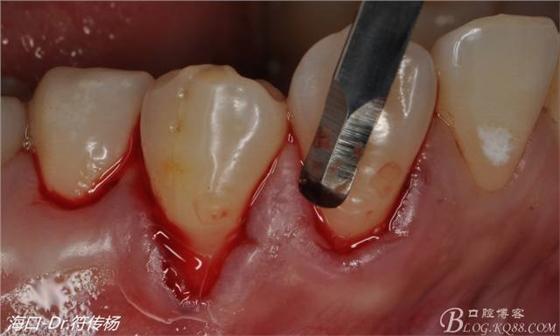

首先用顯微手術(shù)刀切斷手術(shù)范圍內(nèi)的牙周韌帶